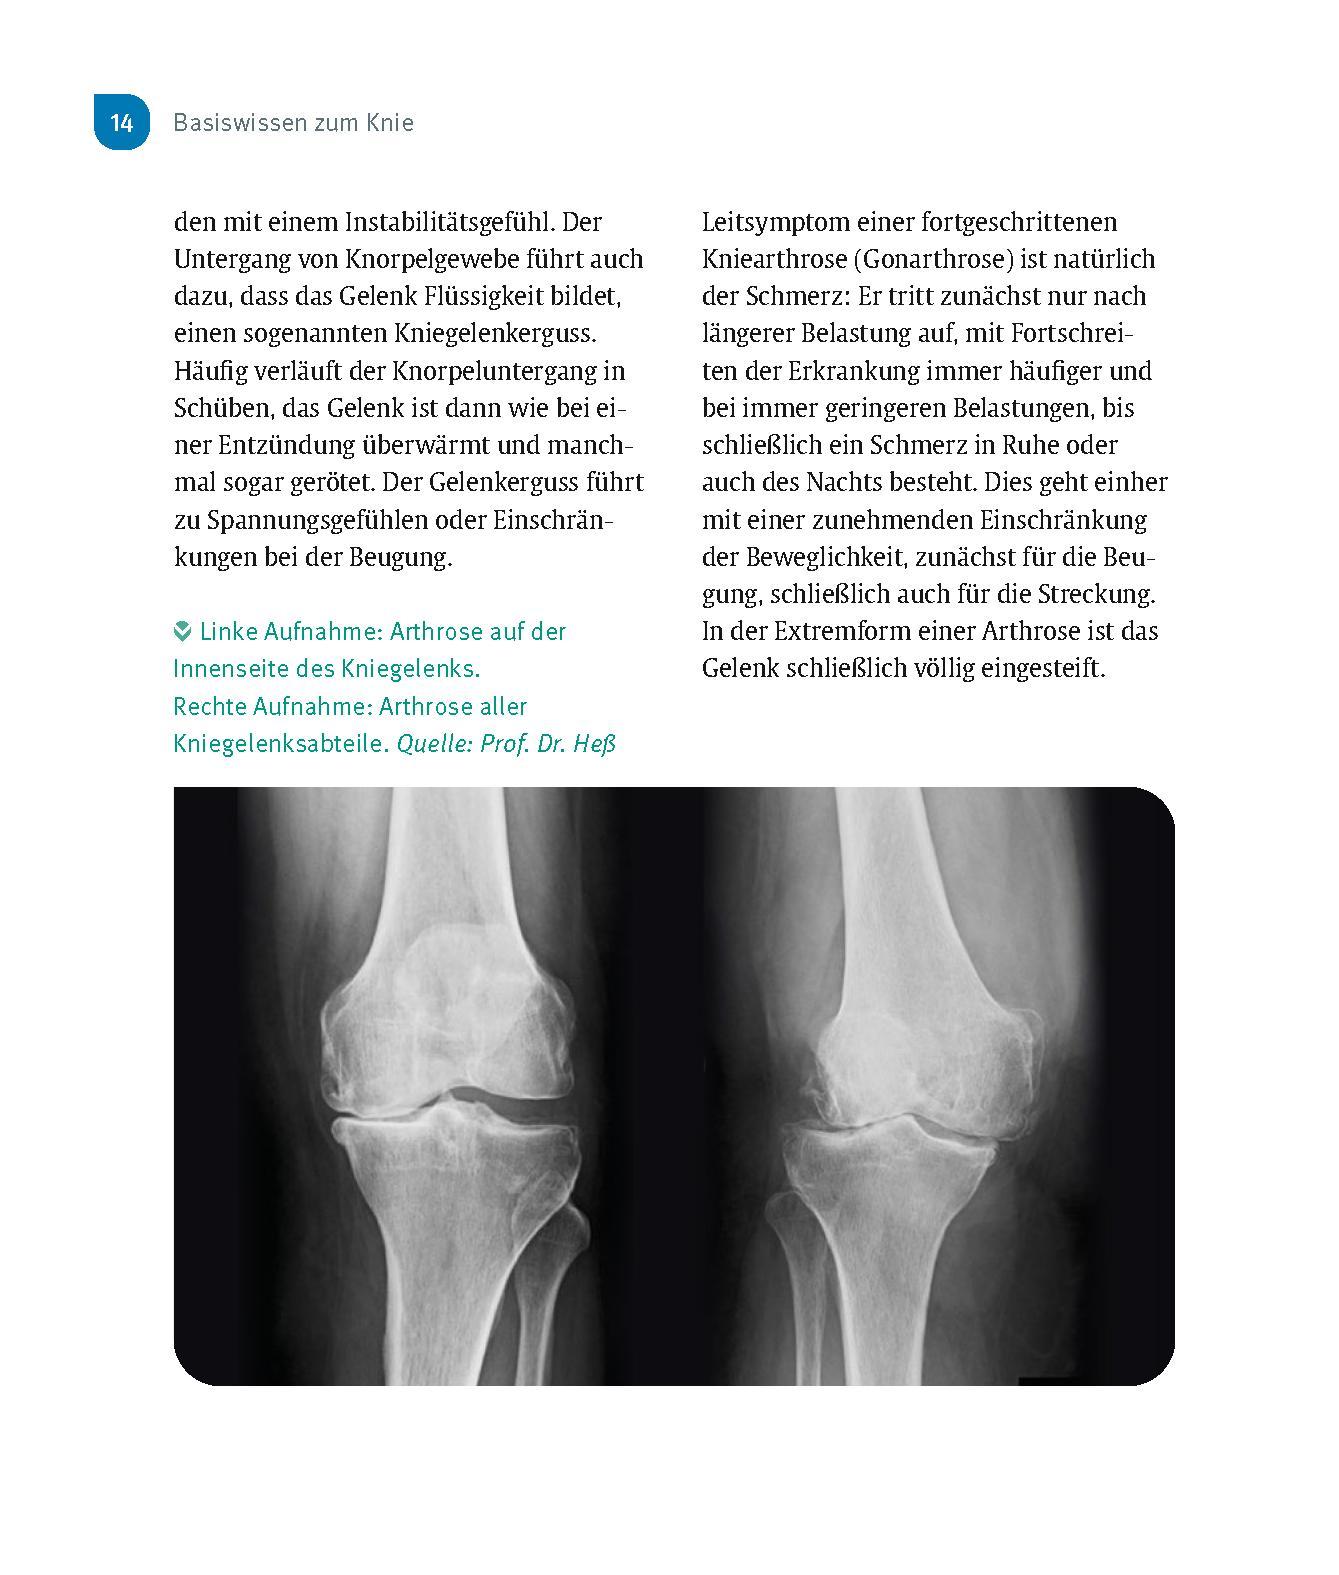

Knie ohne Schmerzen Bei Arthrose im Knie kann ein künstliches Kniegelenk die Lösung sein, um wieder beschwerdefrei gehen zu können. Doch viele haben Angst vor einer Knie OP, auch wenn ihre Gonarthrose große Schmerzen verursacht. Diese Angst wollen die Autoren Ihnen nehmen: Ihre Knie in guten Händen: Prof. Dr. Thomas Heß, Spezialist für Knie OPs, und Silke Rödig, Physiotherapeutin in einer Rehaklinik, stehen für Kompetenz rund um Ihre Knieprobleme. Gut vorbereitet in die OP: Alle wichtigen Hintergründe über Arthrose, künstliche Gelenke und den Eingriff. So werden Sie schnell wieder fit: Schmerzlindernde Nachsorge und die besten Übungen nach der Knie OP für zu Hause. Endlich wieder schmerzfrei laufen!